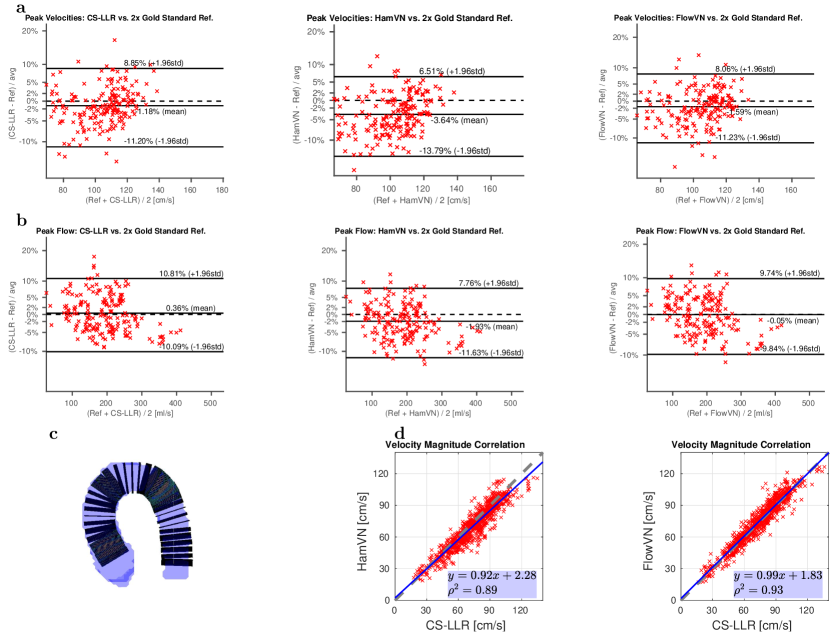

The prospective undersampling acquisition results are reported in Fig. 5a,b: peak velocities and peak flow estimated using CS-LLR and FlowVN are in good agreement with PI reconstruction, while HamVN systematically underestimates velocity magnitudes. Moreover, correlation analysis in Fig. 5d reveals high correlation between CS-LLR and FlowVN velocity estimates. In contrast, HamVN shows systematic velocity underestimation, compared to CS-LLR.

Prospective Study

Using manual aorta segmentations we compute flow over cross sections of the aorta by integrating velocity components projected onto the cross section normal. The peak flow is then defined as the maximal flow over cardiac phases for a given cross section. Moreover, we calculate peak through-plane velocity defined as maximum velocity projection across cross sections of the aorta over cardiac phases.

To quantify agreement with the reference 2 PI reconstruction, we performed Bland-Altman analysis 47 of peak flow and peak through-plane velocities.